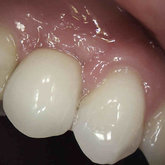

He received his Diploma in Implantology in 2016 from the University of Pretoria, which he passed with Distinction. He is also a member of the International Team for Implantology (ITI), which is based in Switzerland and offers members access to the latest research and cutting-edge techniques.

Porcelain crowns and restorations made in one appointment.

We make it a priority to incorporate the latest in dental technology in everything we do at our practice. ...